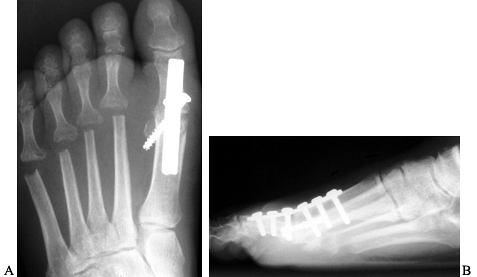

Figure 112.15. AP (A) and lateral (B)

radiographs demonstrating an arthrodesis of the first

metatarsophalangeal joint in a patient with rheumatoid arthritis. The

fusion site should be placed in approximately 15° of valgus, and at 10°

to 15° of dorsiflexion in relation to the ground.